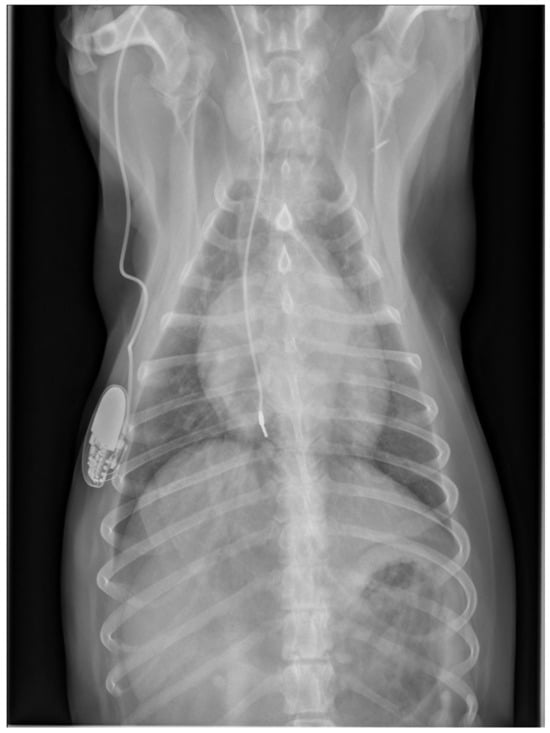

At the next check-up a week later, the owner reported a gradual worsening of appetite and exercise tolerance, while frequent coughing remained unchanged. Every coughing episode was followed by gagging. In addition, the owner reported an increased respiratory rate at rest, frequent panting, and episodes of weakness during walks. Physical examination revealed a slightly depressed dog with an increased respiratory effort and a respiratory rate of 52 breaths/min. The femoral pulses were irregular with a rate of 60 beats/min. Rectal temperature was 38.6 °C. Thoracic radiographs were repeated, which showed a mild diffuse broncho-interstitial lung pattern, sternal lymphadenopathy and increased diameter of the lobar pulmonary arteries to the right cranial and right caudal lung lobes (Figure 6).

Figure 6.

Thoracic radiographs of a dog with chronic cough, hyperthermia and increased respiratory rate and effort show unchanged position of the pacemaker electrode compared to the direct post-operative radiographs. The open arrows indicate the prominent pulmonary artery branches to the right cranial and right caudal lung lobes.